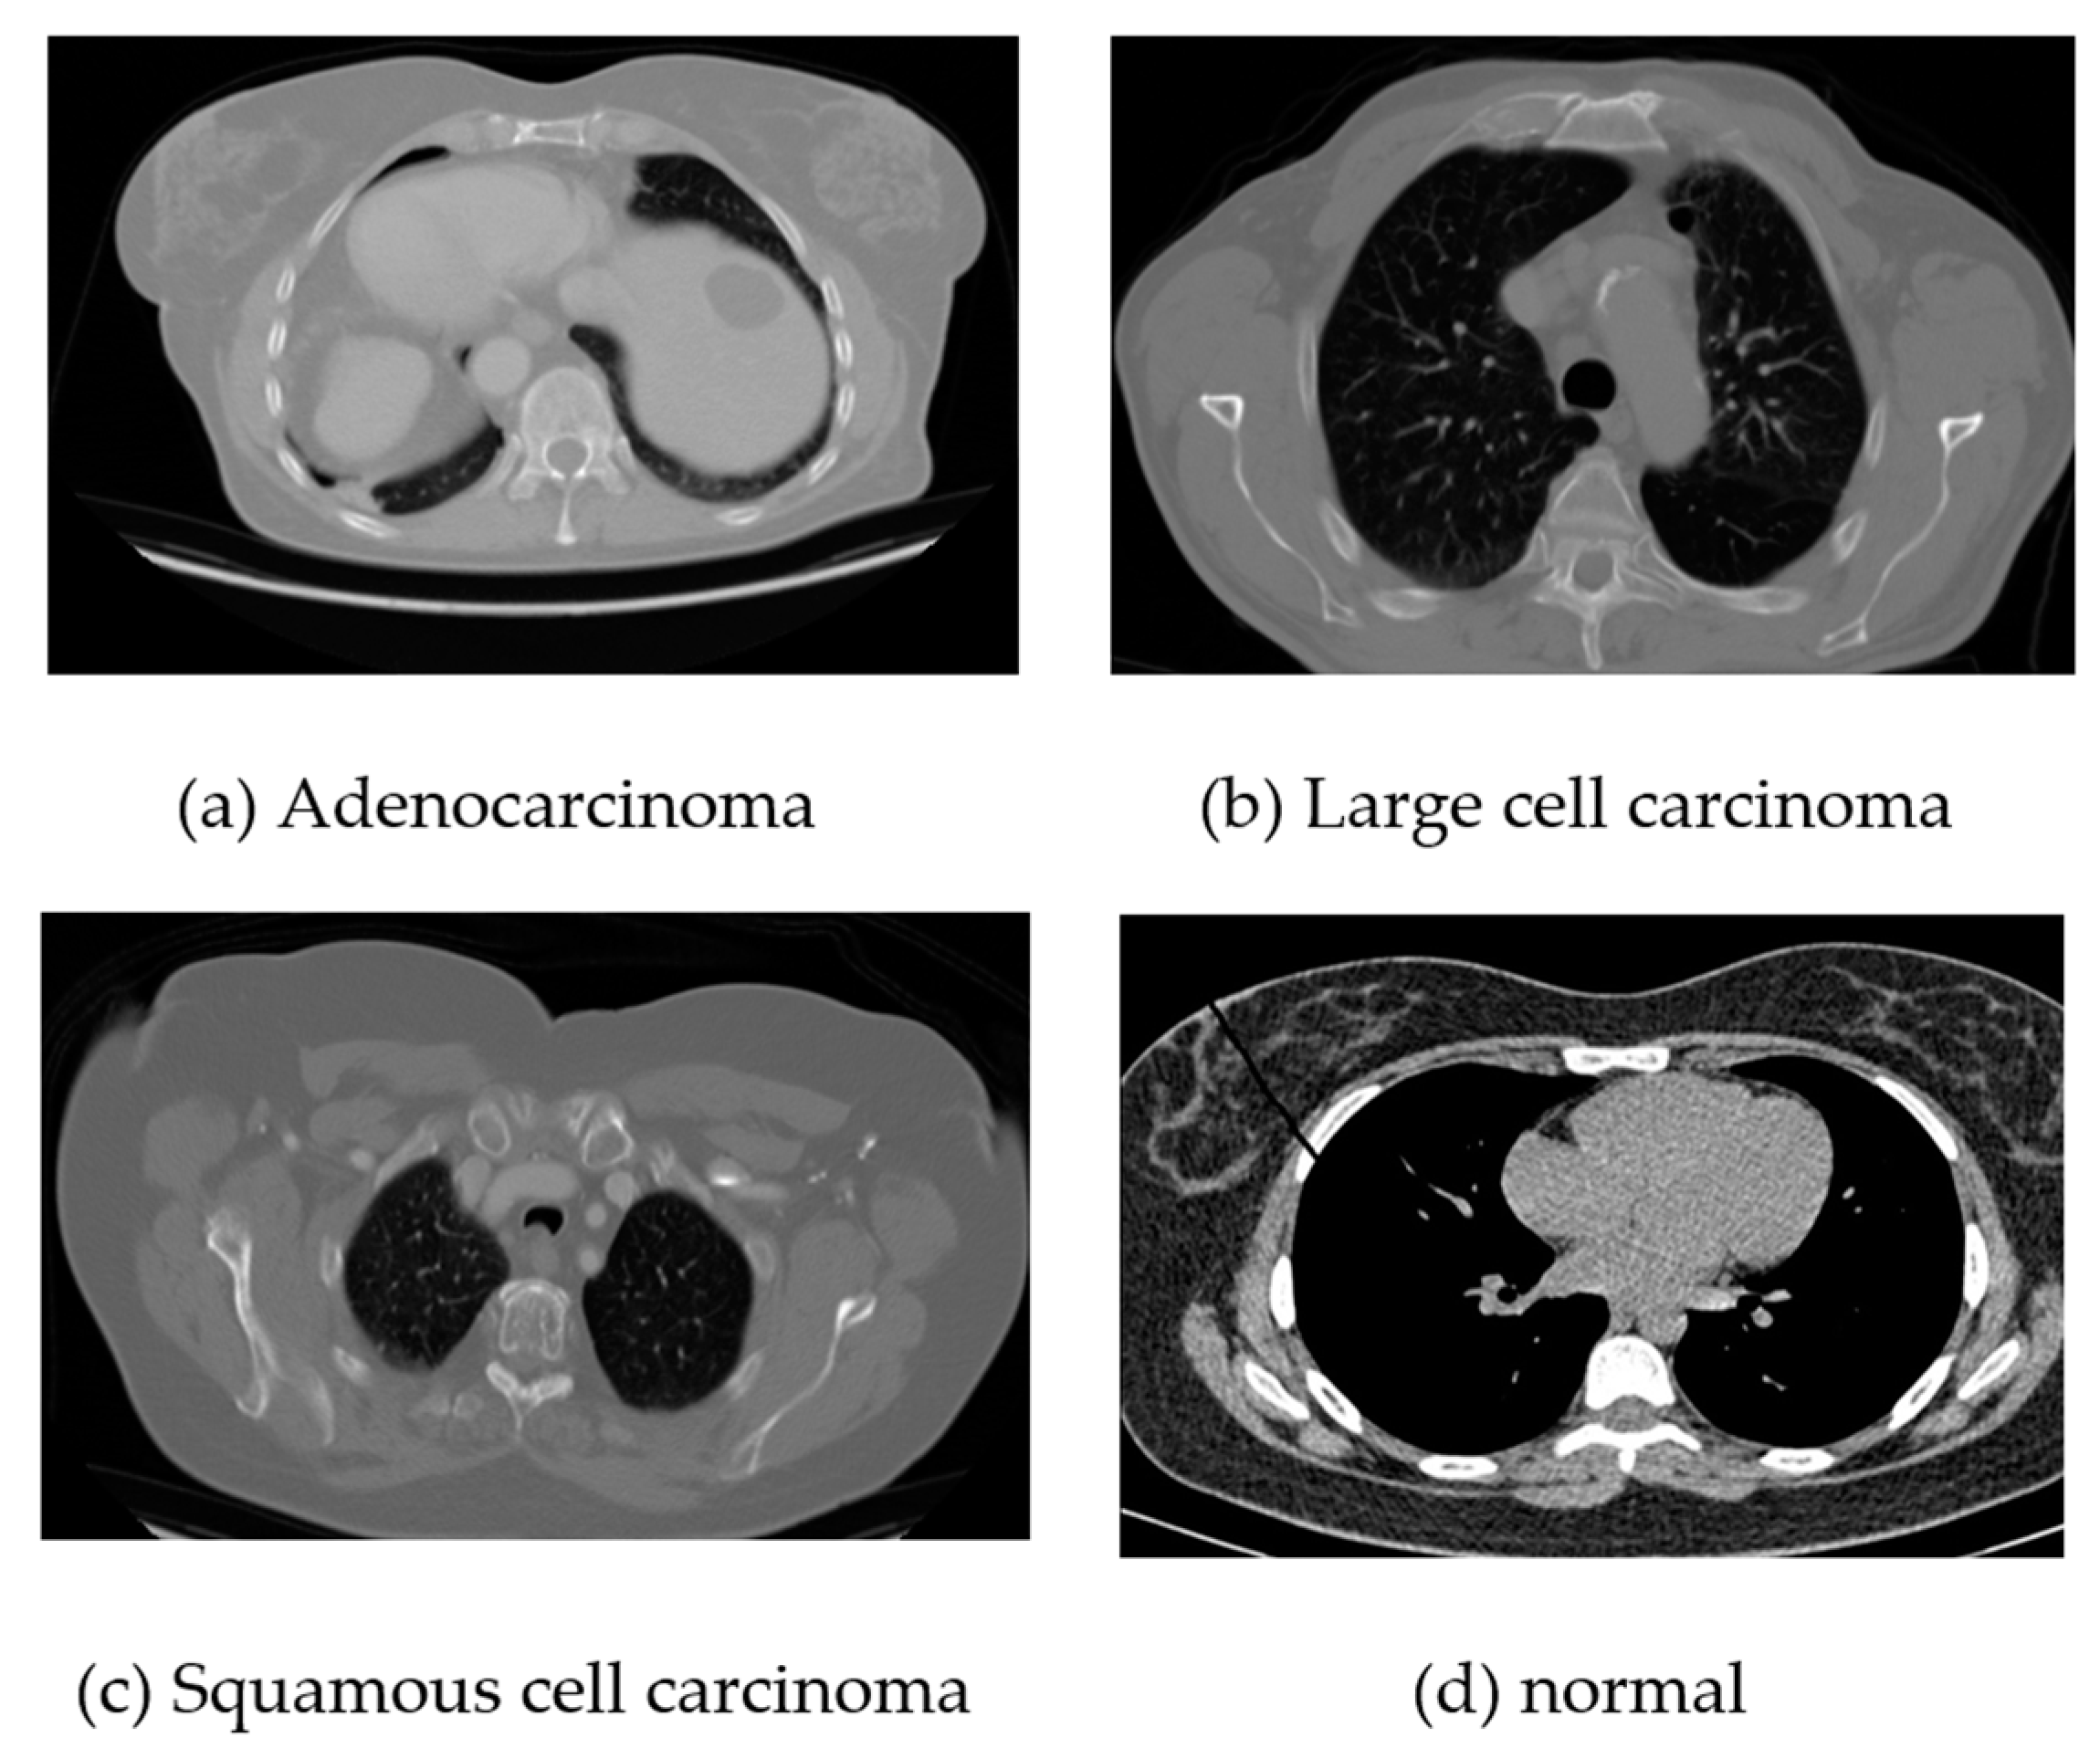

For the chest CT scan images, we consider three classes of cancer and a normal class. Among the cancer classes, there are three types: adenocarcinoma, large-cell carcinoma, and squamous cell carcinoma. A total of 340 images for each class including the normal class have been used for training and testing.

Figure 2 presents sample images from these classes.